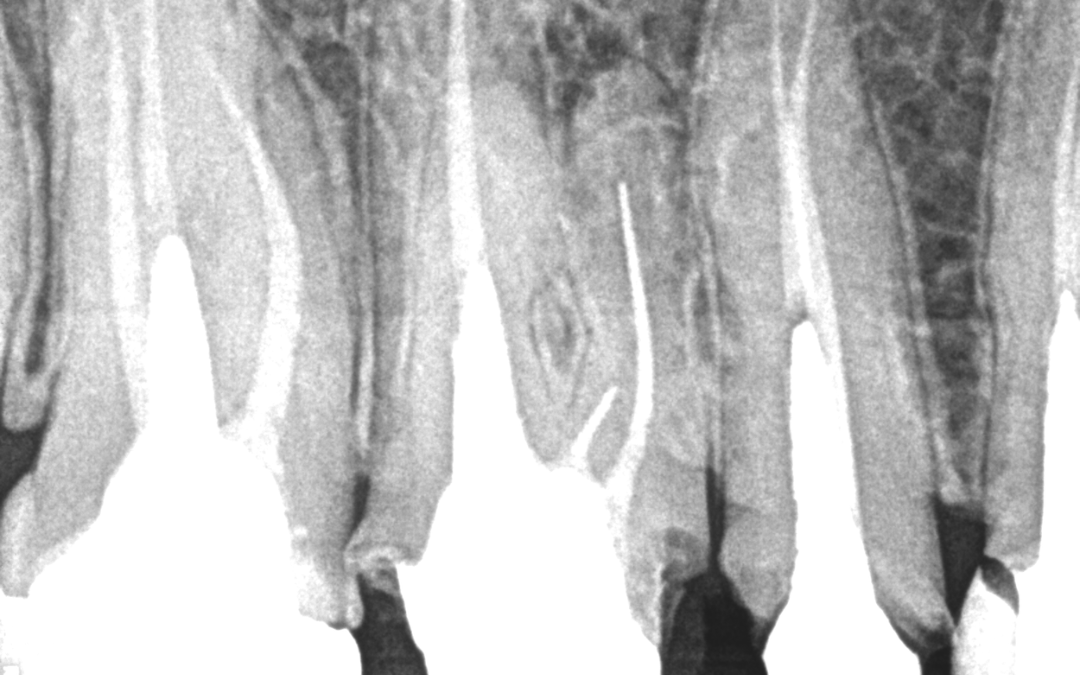

Dente 16 – Remoção de peça, pino metálico, limas fraturadas nos canais mv, mv2 e dv. Para a remoção de lima fraturada ou qualquer outro instrumento endodôntico fraturado dentro do canal, o mais importante de todos os equipamentos utilizados é o Microscópio...